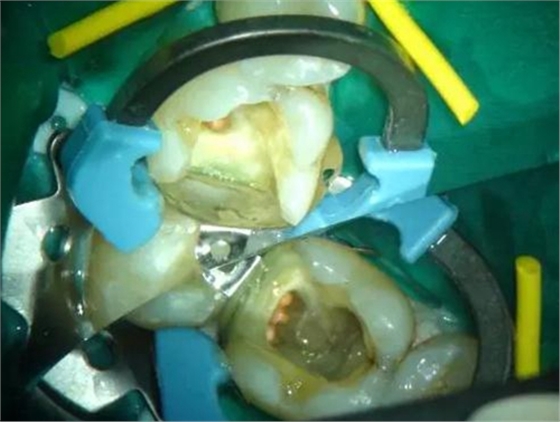

圖1 磨牙根管治療后進行核修復。Palodent V3節(jié)段型成型片、分牙器及楔子均已就位。成型片不會受到橡皮障的影響。可以看到遠中洞型底部成型片的良好貼合。窩洞已酸蝕及涂布粘接劑,牙面呈“潮濕”狀態(tài)。使用橡皮障更利于術(shù)區(qū)濕度控制。然后向窩洞注射SDR。要注意避免:粘接劑在根管口堆積。SDR注射針頭可以探入根管口。雖然SDR的固化深度是4mm,但是建議現(xiàn)在根管口及髓底涂布薄層SDR并固化。此處位置太深,光固化燈可能光強不夠。然后再疊加SDR,直至低于洞緣2-3mm。